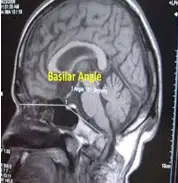

Basilar Kyphosis

به کاهش زاویه بازال (Basal Angle: N-S-Ba) کرانیال بیس گفته می شود. .همچنین به افزایش بیش از حد این زاویه، Platybasia گفته می شود.

Normal: 125°-143°

Platybasia: > 143°

Basilar kyphosis: < 125°